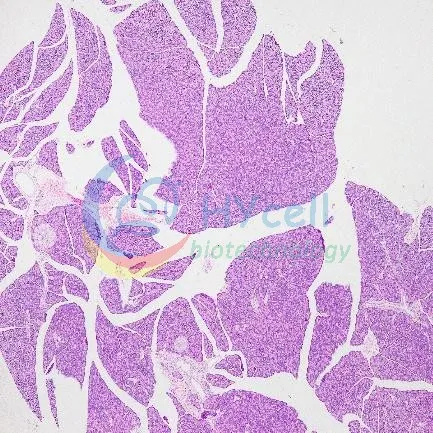

HE染色

| 正常组 | 模型组 |

HE染色结果:与正常组相比,模型组胰腺小叶结构相对紊乱,部分腺泡肿胀坏死、结构模糊、边界不清晰,胰腺间质有炎细胞浸润和红细胞渗出。